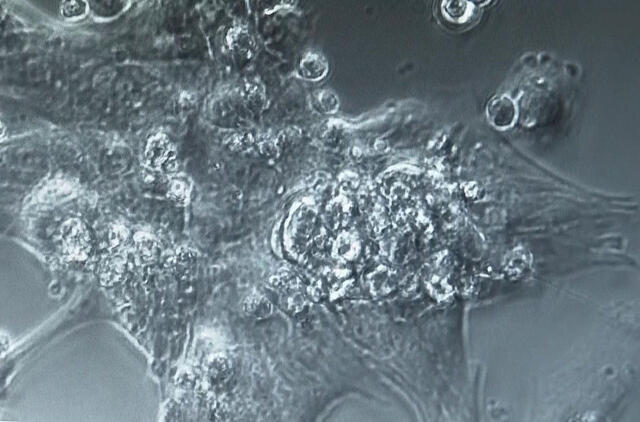

Laboratorijoje užaugintos širdys, vadinamos organoidais, yra pagamintos iš žmogaus kamieninių ląstelių ir sunaikinamos po 28 dienų.

Mokslininkai laboratorijoje augina širdies ląsteles, kad sukurtų dirbtinio intelekto įrankį, galintį greičiau aptikti širdies ląstelių ligas.